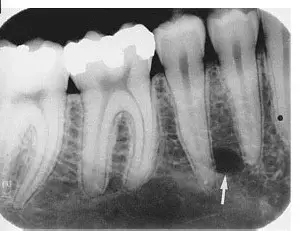

radiographs or digital radiography

what must be visualised when using radiographs

morphological features of the pulp chambers and root canals

what has to happen to visual the features

3D features are compressed into 2D radiographic images

radiographic views from a facial orientation show what type of view

a monoplane, buccolingual view of hard tooth structures and radiolucent spaces for the pulp canals

what colour is the pulp and hard tissue (enamel)

pulp = darker